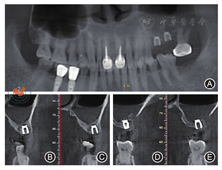

。锥形束CT(cone beam computed tomography,CBCT)示:25、26牙槽嵴高度0.9~ 2.1 mm,左侧上颌窦可见弥漫性大小为27.6 mm × 16.2 mm低密度影(图1)。诊断:上颌牙列缺损。治疗方案:行牙周基础治疗;保留上颌窦囊肿的前提下行上颌窦外提升骨增量术,待25、26区牙槽嵴高度足够时再行Ⅰ期牙种植手术。

注:图1A为初诊时的全颌曲面断层影像;图1B~ 1C为25唇颊侧切面;图1D~ 1E为26唇颊侧切面